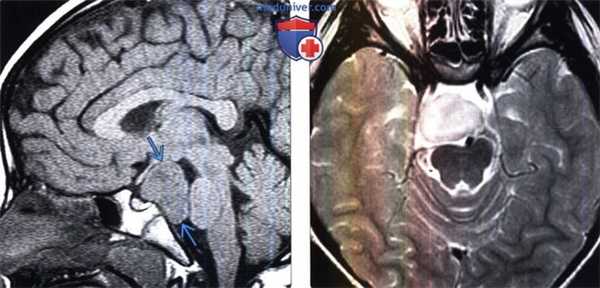

(Слева) На рисунке сагиттальною среза показана классическая гамартома серого бугра на ножке, расположенная между воронкой спереди и сосцевидными телами сзади. Данное объемное образование схоже с серым веществом.

(Справа) МРТ, Т1-ВИ, сагиттальный срез: у восьмилетней девочки с преждевременным половым созреванием визуализируется классическая гамартома гипоталамуса на ножке по типу «запонки». Это образование расположено между воронкой гипофиза спереди и сосцевидными телами сзади. Классическая гамартома гипоталамуса (ГГ) имеет изоинтенсивный сигнал по отношению к серому веществу. (Слева) МРТ, Т2-ВИ, сагиттальный срез: у пациента с преждевременным половым созреванием определяется объемное образование гипоталамуса на ножке, расположенное между срединным возвышением и сосцевидными телами. Данное образование имеет изоинтенсивный по отношению к коре сигнал.

(Справа) МРТ, постконтрастное Т1 -ВИ, сагиттальный срез: у этого же пациента отмечается отсутствие накопления контраста объемным образованием. Это классический случай гамартомы гипоталамуса (ГГ) на ножке.

(Слева) МРТ, Т1 -ВИ, сагиттальный срез: у ребенка с преждевременным половым созреванием определяется крупное дольчатое супраселлярное объемное образование, изоинтенсивное по отношению к коре и отчетливо не связанное с гипофизом и зрительным перекрестом. Это образование имеет настолько крупные размеры, что смещает ствол мозга кзади.

(Справа) МРТ, Т2-ВИ, аксиальный срез: у этого же пациента отмечается неоднородно гиперинтенсивное по отношению к коре объемное образование. Гамартома гипоталамуса (ГГ) может достигать нескольких сантиметров в диаметре. Это образование было удалено, оно состояло из дисплазированного и дезорганизованного серого вещества и соответствовало гамартоме гипоталамуса (ГГ).